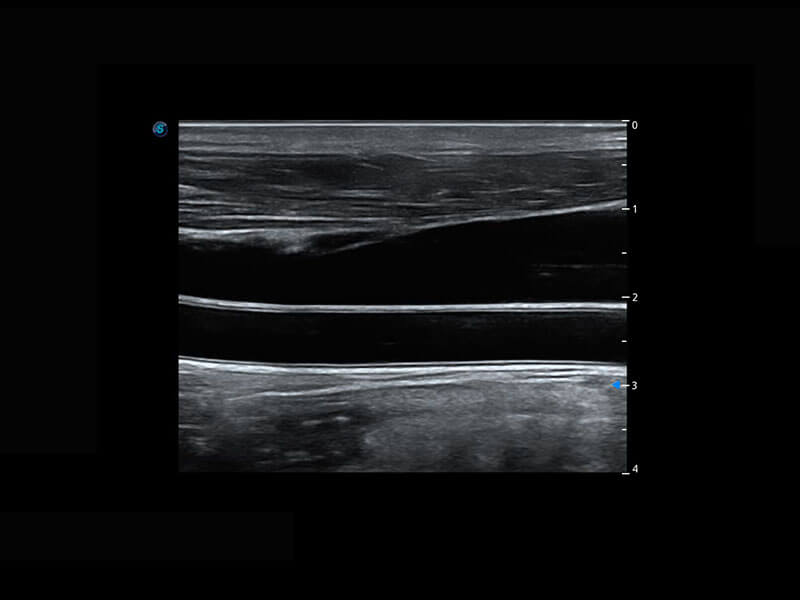

P60搭載寬頻帶線陣探頭、寬景成像、彈性成像技術(shù),為您提供乳腺應(yīng)用方案。P60支持高頻相控陣探頭、線陣探頭、腹部高頻探頭、腹部微凸探頭等,豐富的探頭群搭載敏感的彩色血流成像,適用于新生兒多種臟器檢測要求,滿足新生兒篩查需求。

乳腺導(dǎo)管癌

乳腺癌顯微血流